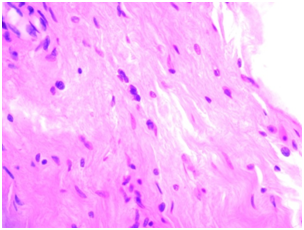

Fascia lata-during histological research was presented as a narrow plate of friable connective tissue stained with eosin evenly, with the presence of a few spindle-shaped fibroblasts with rod-shaped core. No signs of inflammation (Figure 2).

During the iimmunohistochemical study of the reaction with type IV collagen marker was negative, indicating the absence of pathological types of collagen, but for the full picture of the collagen matrix, a reaction to collagen type-I is necessary. There was a weak-positive reaction to CD34 and MMP-9, which indicates the ongoing processes of vascularization and collagenization in transplanted graft. CD3 and CD20 were not detected, indicating that there was no inflammation.